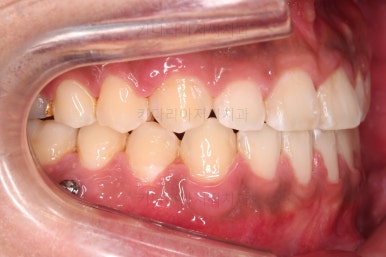

가지런한 느낌, 앞니 뻐드러짐을 좋게 했고요.

교합도 맞춰 위아래가 톱니바퀴처럼 맞물리게 했고, 앞니도 위아래 관계를 잘 맞추고 마무리를 했습니다.

전후 비교해 볼게요.

1년 3개월이라는 비교적 짧은 기간안에 적절한 교합, 심미성 등 여러 가지를 달성했던 만족스러운 치료였습니다.

이상 비수술, 비발치로 주걱턱 및 앵글씨 3급 부정교합을 개선했던 부산교정 치료사례였습니다.